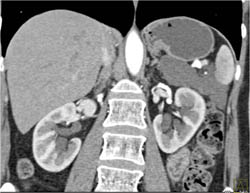

Lymphangioma